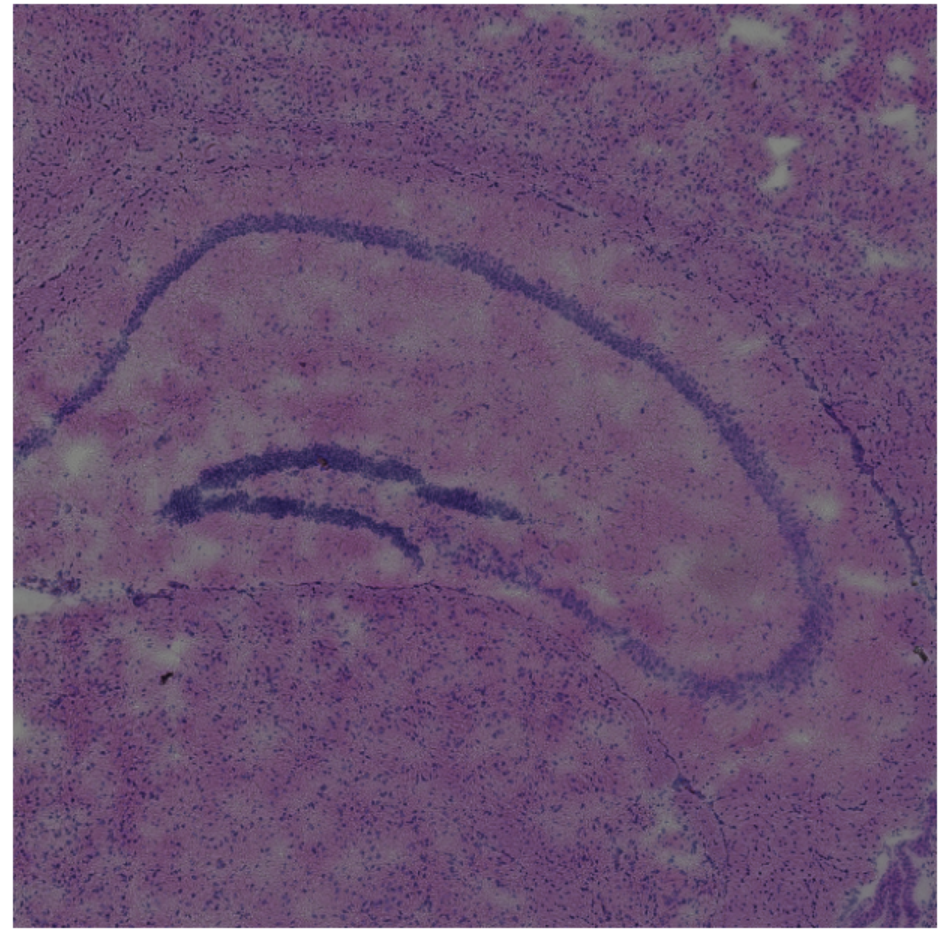

In spite of the fact that these steps did not incorporate the use of spatial coordinate information, the algorithms successfully partitioned the tissue into sections visually coherent with the histological image. In particular, Cluster 8 forms the distinct C-shaped structure of the Dentate Gyrus.

To further validate the identification of this region, differential expression analysis using a "One vs Rest t-test" was conducted. The C1ql2 gene was identified as the most significantly different marker when compared to other clusters. Since C1ql2 is a known marker of the Dentate Gyrus, we can therefore confirm both visually and biologically that the algorithm pipeline had correctly identified the Dentate Gyrus.